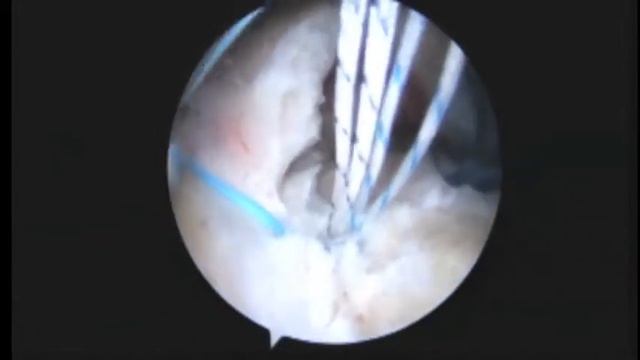

DS R Arthroscopic Rotator Cuff Repair Of Large Tear And Biceps Tenodesis 1 8 15

DS R Arthroscopic Rotator Cuff Repair Of Large Tear And Biceps Tenodesis 1 8 15 - 11.01.2024

Подготовка женского тела к вершинам